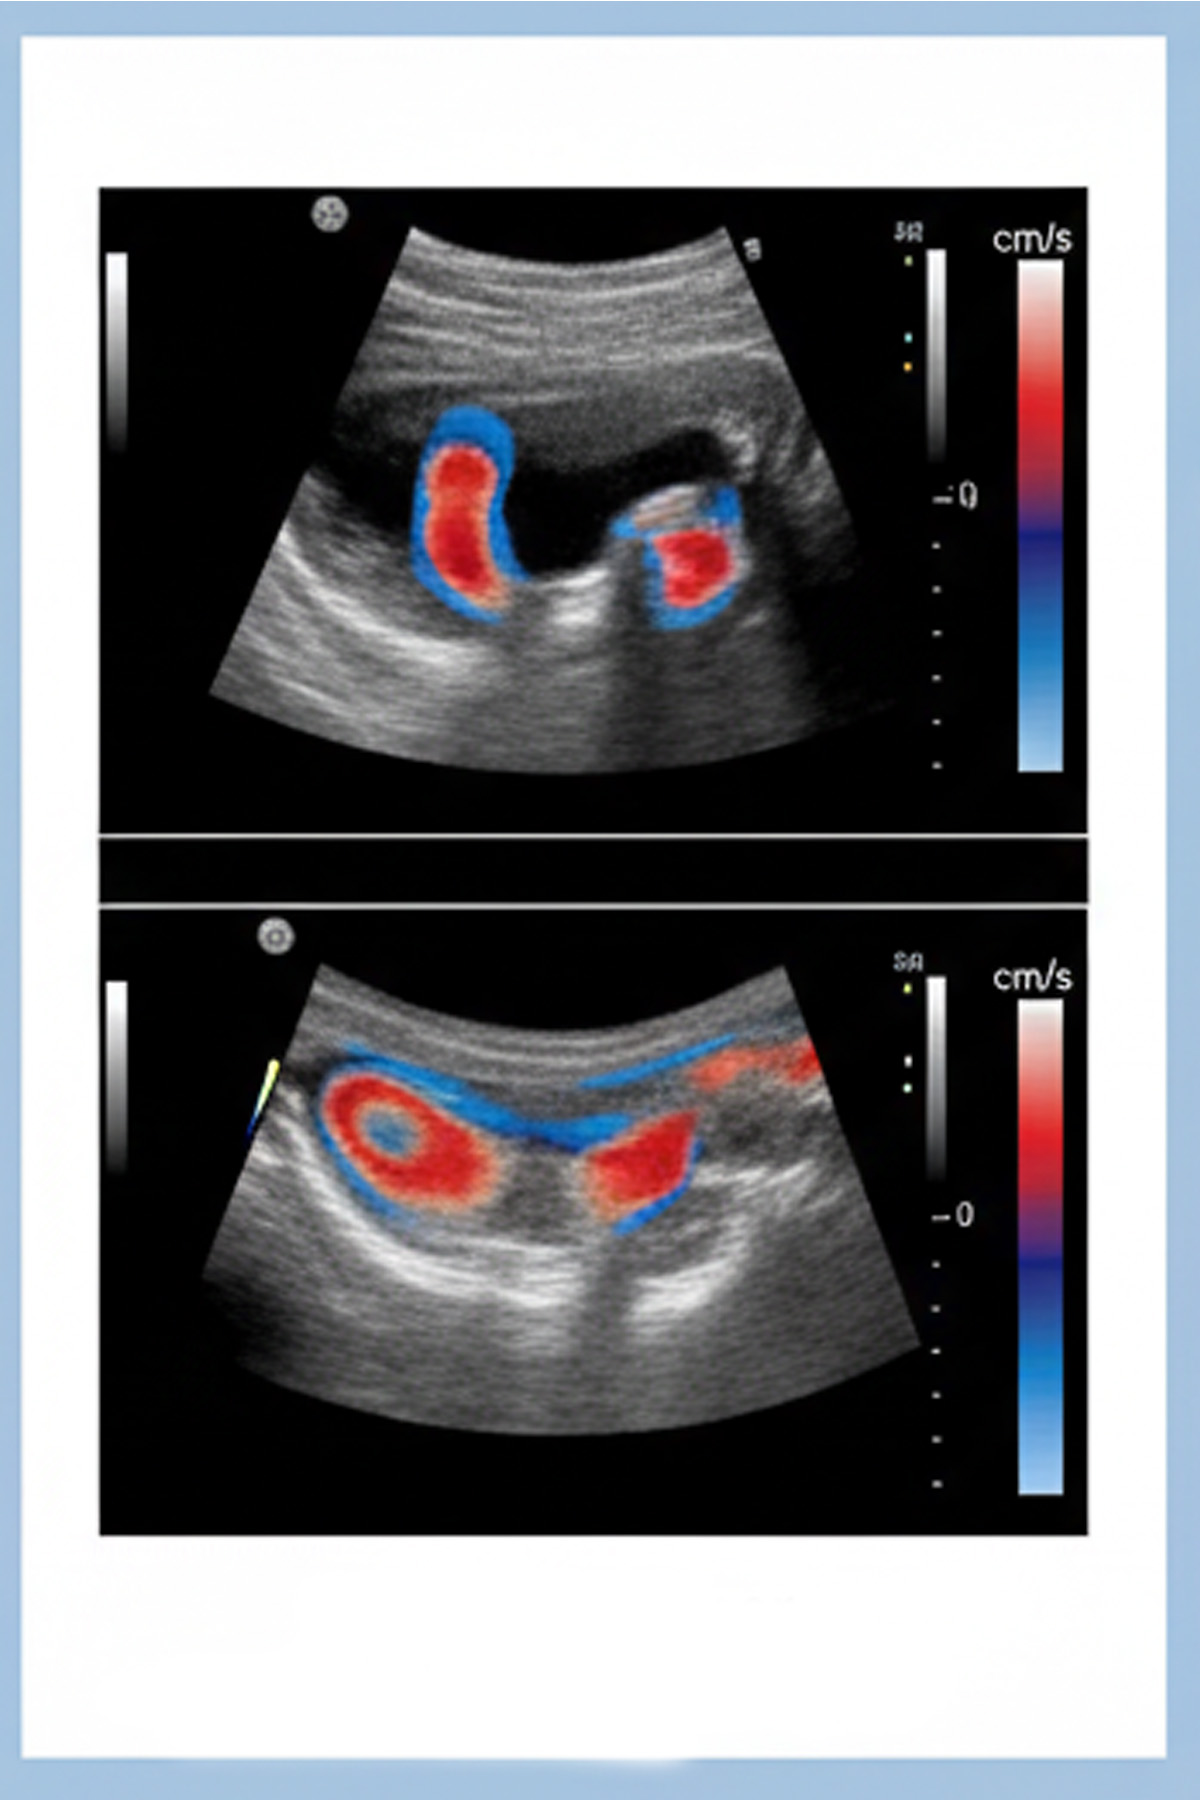

Echocardiography and vascular doppler

Ultrasonido Vascular Periférico (Doppler Vascular)